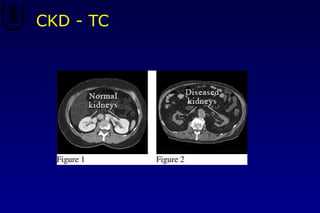

CKD - TC